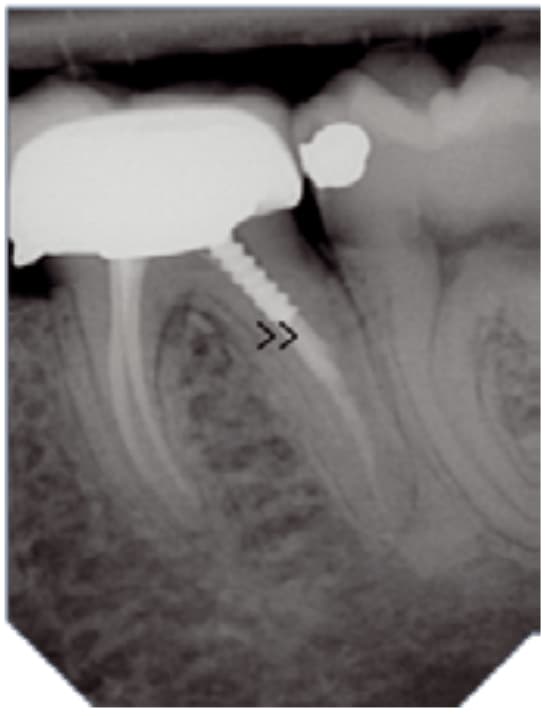

Wysoka rozdzielczość zapewnia dokładną i niezawodną diagnostykę. Technologia wielowarstwowa zapewnia obrazy o niskim poziomie szumów i z wyjątkową ostrością – w zaledwie kilka sekund.